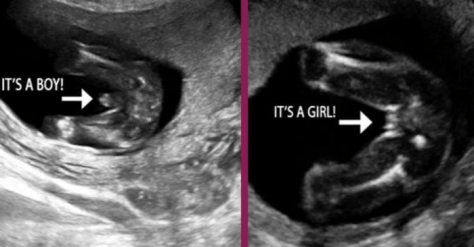

На цьому етапі також можливо визначити стать дитини (хлопчик чи дівчинка).